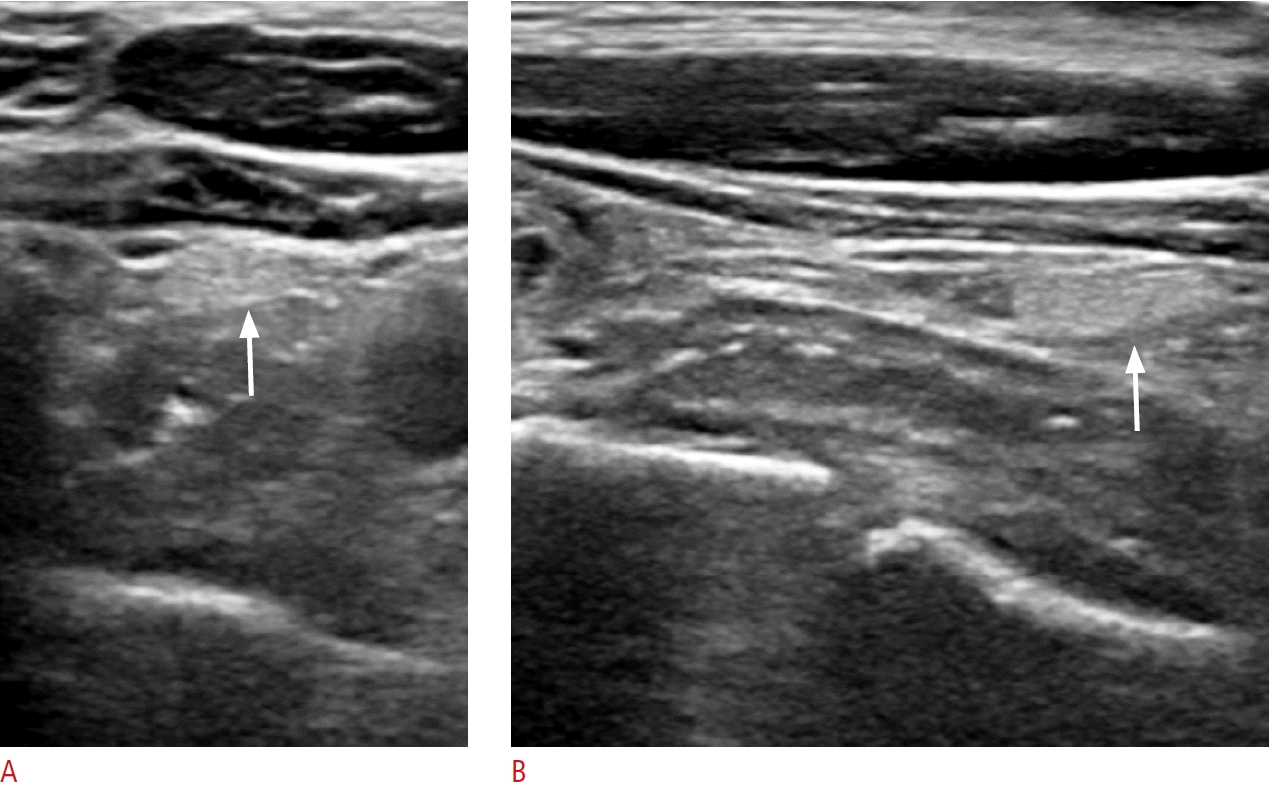

Fig. 2.

Normal parathyroid gland with typical ultrasound features in the inferior posterior perithyroidal central neck in a 65-year-old male patient (case 1).

A, B. Transverse and longitudinal images show an ovoid, homogeneous, markedly hyperechoic parathyroid gland brighter than the thyroid gland at the inferior posterior margin of the left thyroid gland (arrows).